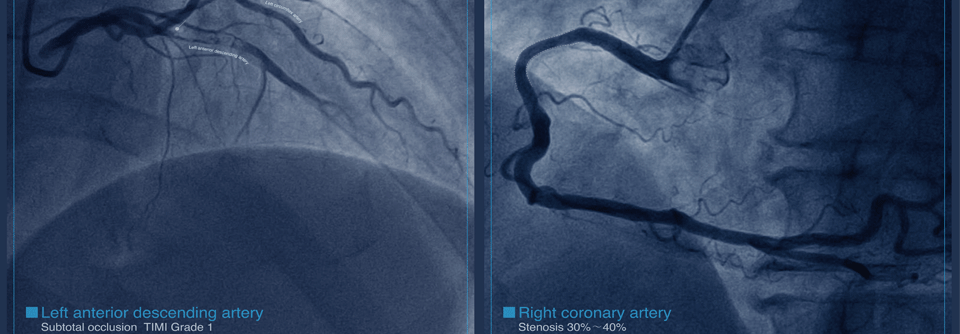

Die Frage, wie es um die Prognose rauchender KHK-Patientinnen und -Patienten bestellt ist, die nach perkutaner Koronarintervention (PCI) auf E-Zigaretten umgestiegen sind, war Ausgangspunkt einer Kohortenstudie. Als Grundlage diente die Datenbank der koreanischen Krankenversicherung.

In die Analyse flossen die Informationen zu knapp 18.000 Raucherinnen und Rauchern im Alter ab 20 Jahren ein, die sich jeweils in den drei Jahren vor und nach einer PCI einem Gesundheitscheck unterzogen hatten. Fast 9.000 von ihnen griffen nach der PCI weiterhin zum Glimmstängel, knapp 1.700 wechselten zur E-Zigarette und gut 7.300 stellten das Rauchen erfolgreich ein.

Während einer mittleren Nachbeobachtungszeit von 2,4 Jahren lag die kumulative Inzidenz schwerer unerwünschter kardialer Ereignisse (MACE) in der Gruppe derer, die auf E-Zigaretten gewechselt hatten, bei 10 %. Bei denen, die konventionellen Zigaretten treu blieben, betrug sie 17 % und bei jenen, die mit dem Rauchen aufgehört hatten, 13,4 %.

Der Unterschied im MACE-Risiko zwischen den Personen, die den Rauchstopp geschafft hatten, und den E-Zigaretten-Konsumierenden war nicht signifikant. Die Hazard Ratios (HR) für kardiovaskulären Tod, Herzinfarkt oder eine erneute Revaskularisation gegenüber Weiterrauchenden betrugen 0,82 für den Wechsel auf E-Zigarette und 0,87 für den erfolgreichen Komplettausstieg.

Im Vergleich zu Doppelnutzung (konventionelle plus E-Zigarette) war der vollständige Umstieg auf E-Zigaretten mit einem signifikant geringeren kardiovaskulären Risiko verbunden (HR 0,71), schreibt ein Team um Prof. Dr. Danbee Kang von der Sungkyunkwan University School of Medicine in Seoul. Für Menschen, denen ein Rauchstopp nicht gelingt, könnte Vaping eine Überlegung wert sein.